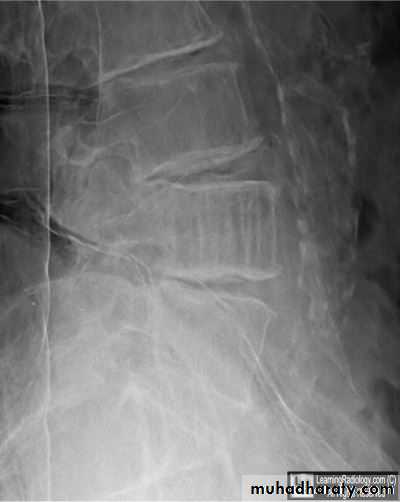

Spondylolysis and spondylolisthesis

Spondylolisthesis is a term denoting fore ward or backward movement of a vertebra relative to the vertebral segment below, typically due to spondylolysis (pars interarticularis defects) .Spondylolysis - “Spondylolysis is a defect in the pars interarticularis of the neural arch, the portion of the neural arch that connects the superior and inferior articular facet in which cause defect in the neck of scotty dog .

scotty dog sign refers to the normal appearance of the lumbar spine when seen on oblique radiographic projection. On oblique views, the posterior elements of vertebra form the figure of a Scotty dog with:

the transverse process being the nose

the pedicle forming the eye

the inferior articular facet being the front leg

the superior articular facet representing the ear

the pars interarticularis (the portion of the lamina that lies between the facets) equivalent to the neck of the dog.